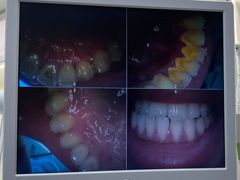

• 牙博士口腔品牌连锁(杨浦店)

• -牙博士口腔品牌连锁(杨浦店)

Jack.Wang | 22-03-14